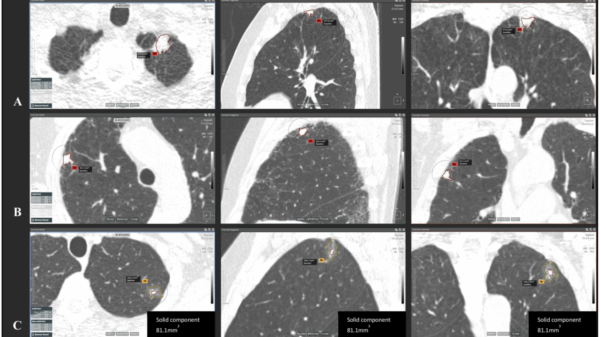

AI and Autonomy AI could help lessen radiologist lung cancer screening workload by up to 79% New research from the University of Liverpool found that it is efficacious for filtering out negative CT scans Rowan DunneMarch 3, 2025